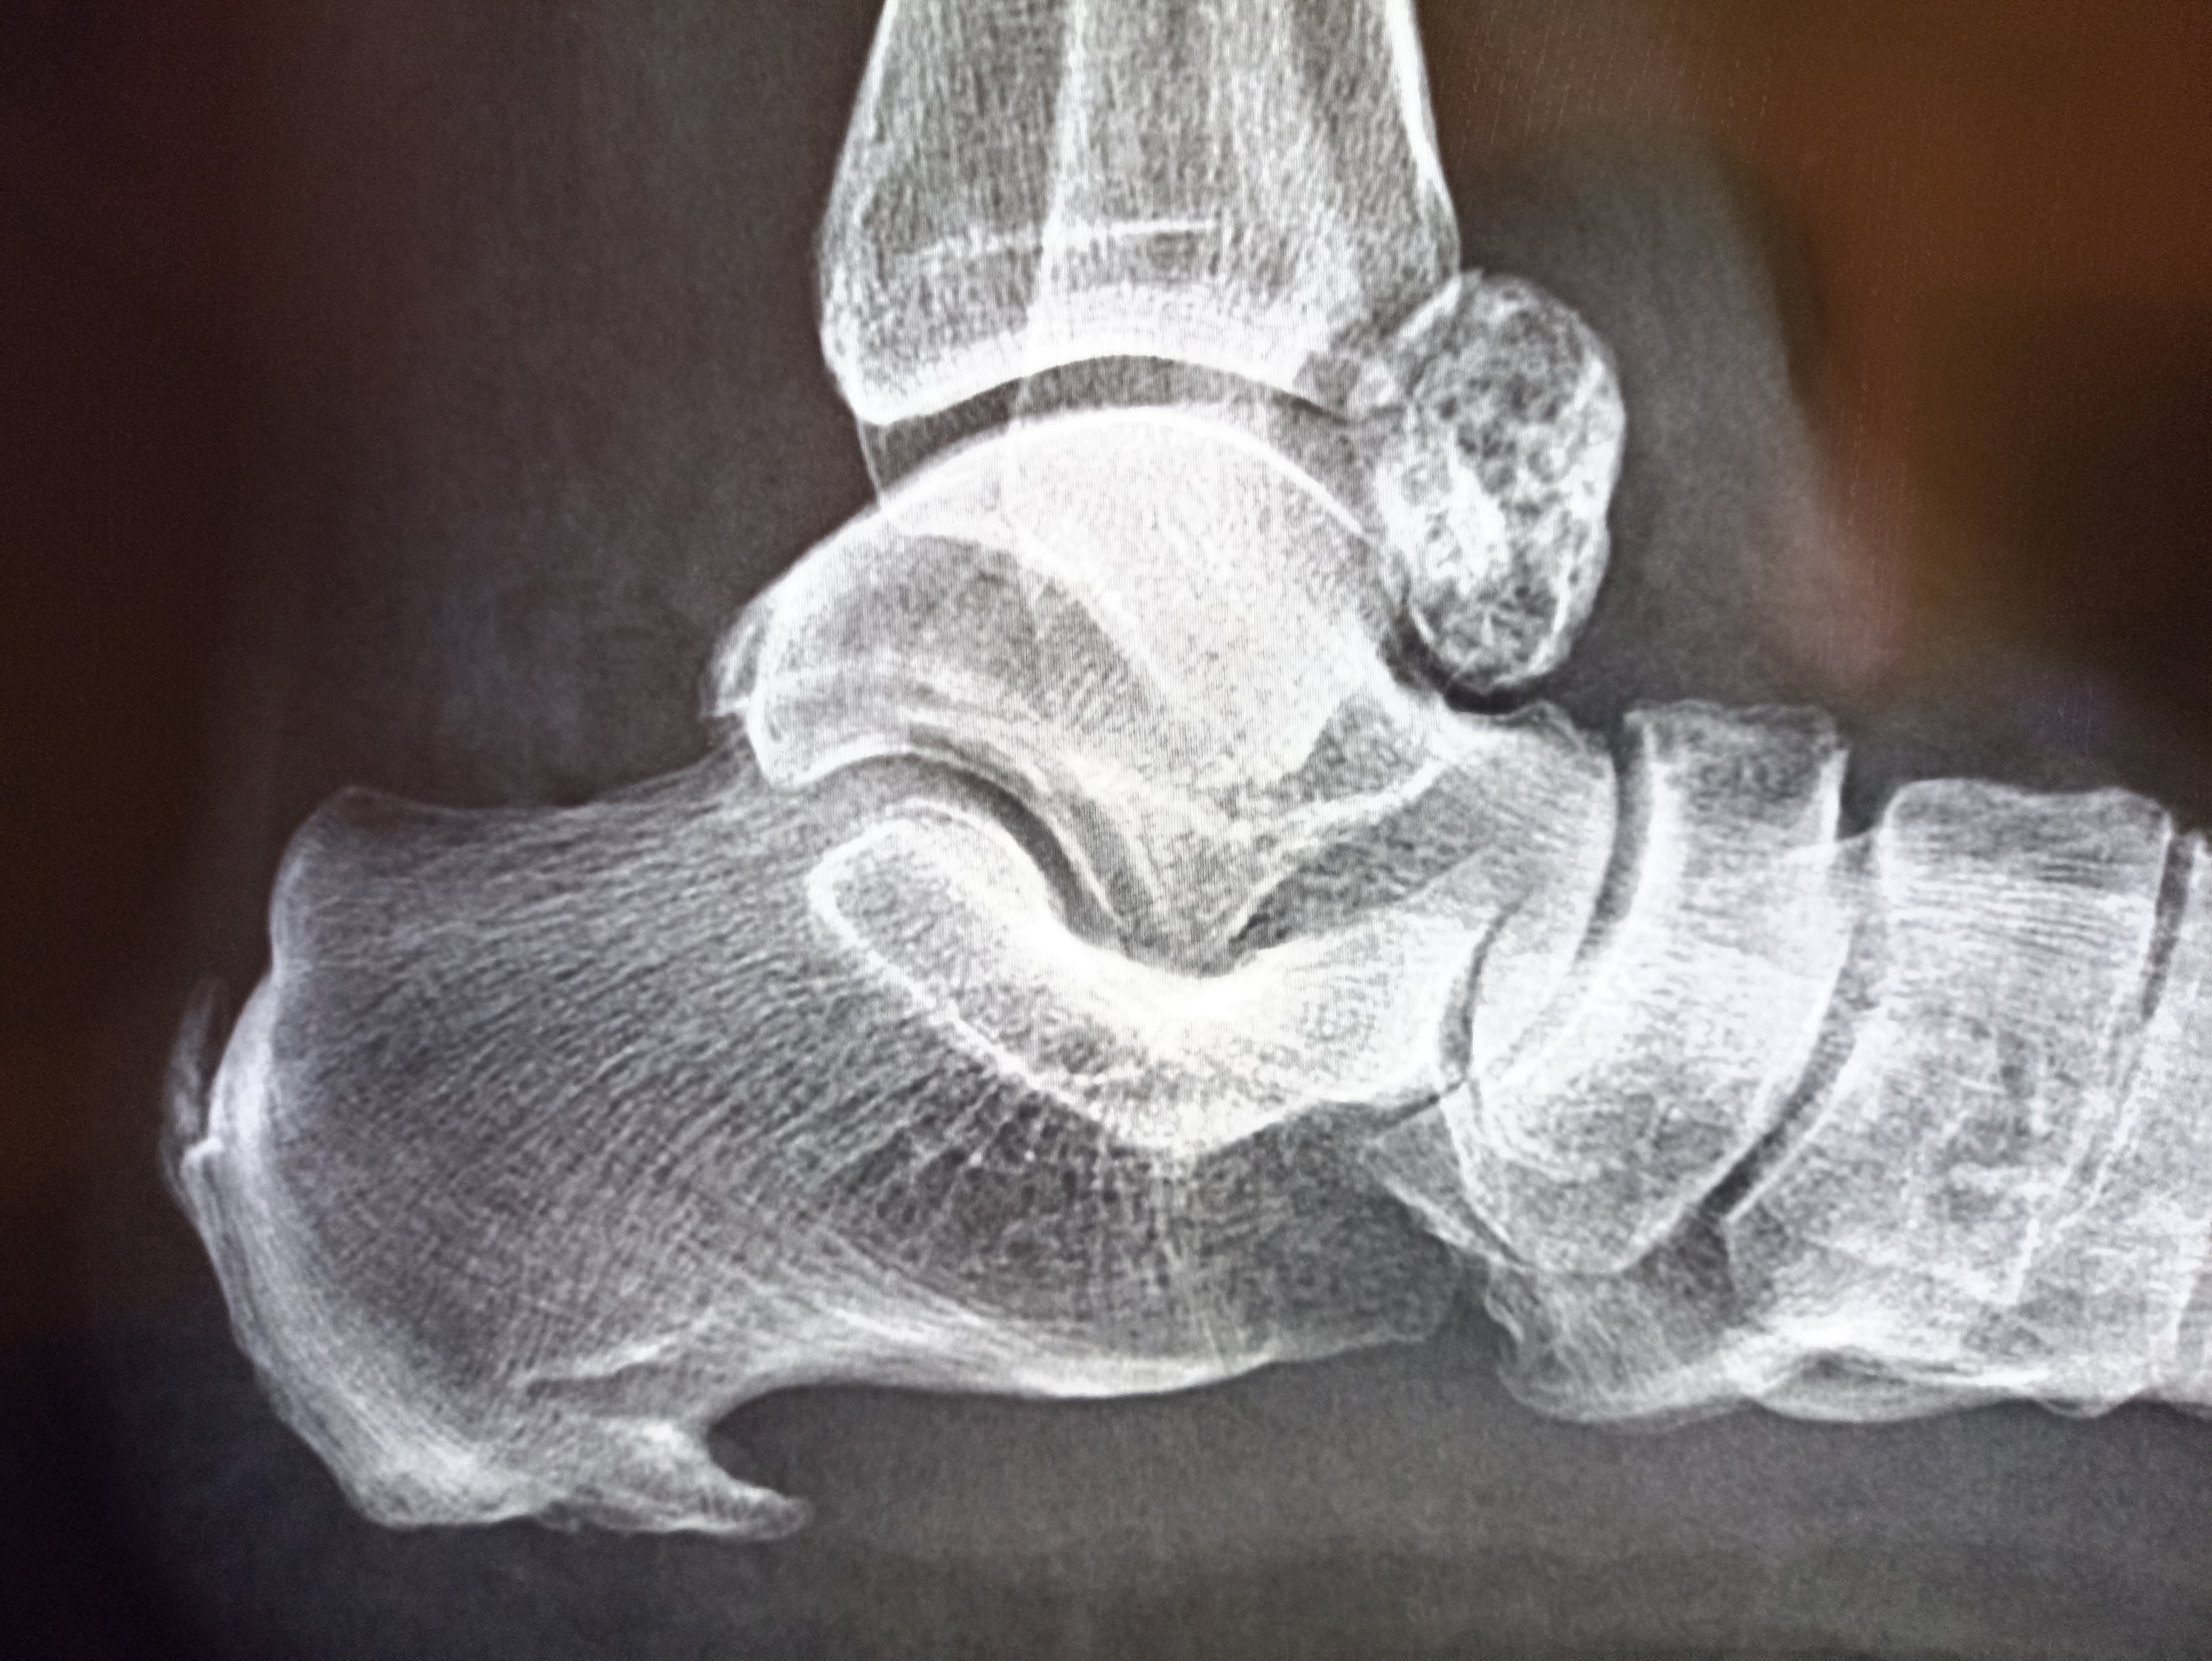

Ну кардиомегалия то там есть конечно, но его беспокит другое.

>>327478302

Рентгенография голеностопного сустава и задних отделов стопы в боковой проекции.

Костная структура дистального отдела большеберцовой кости, таранной и пяточной костей прослеживается отчётливо, трабекулярный рисунок сохранён. Контуры суставных поверхностей в целом ровные, замыкательные пластинки прослеживаются. Суставная щель голеностопного сустава обычной ширины. Признаков острых переломов, грубой деформации или вывиха не определяется.

В проекции заднего отдела голеностопного сустава, кзади от таранной кости, визуализируется дополнительная овальная тень костной плотности с чёткими, местами бугристыми контурами, трабекулярной структурой, контактирующая с костями сустава.

На нижнем крае пяточной кости определяется краевой костный разрастание в области плантарной поверхности (подошвенный остеофит).

Мягкие ткани без грубых рентгенологических изменений.

Заключение

Рентгенологически – дополнительное костное образование в заднем отделе голеностопного сустава (вероятнее всего вариант дополнительной кости/костный разрастание), подошвенный остеофит пяточной кости. Данных за острый перелом и вывих не получено.